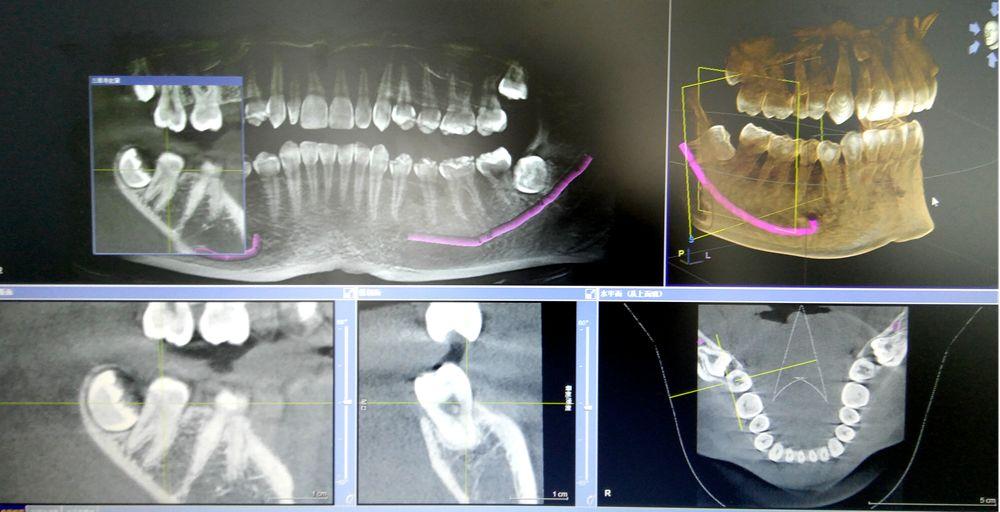

CBCT掃描可準確分析頜骨植入區(qū)的骨質、骨量、骨密度及植體與下頜神經管、上頜竇的關系,臨床醫(yī)生可以在圖像上模擬種植,直接與患者進行溝通及交流,并可指導手術者在手術方案中避開危險區(qū)域,手術的性。此外,臨床醫(yī)生還可以利用CT數據進行數字模型重建,配合軟件預先做好手術模板使種植手術更快捷。